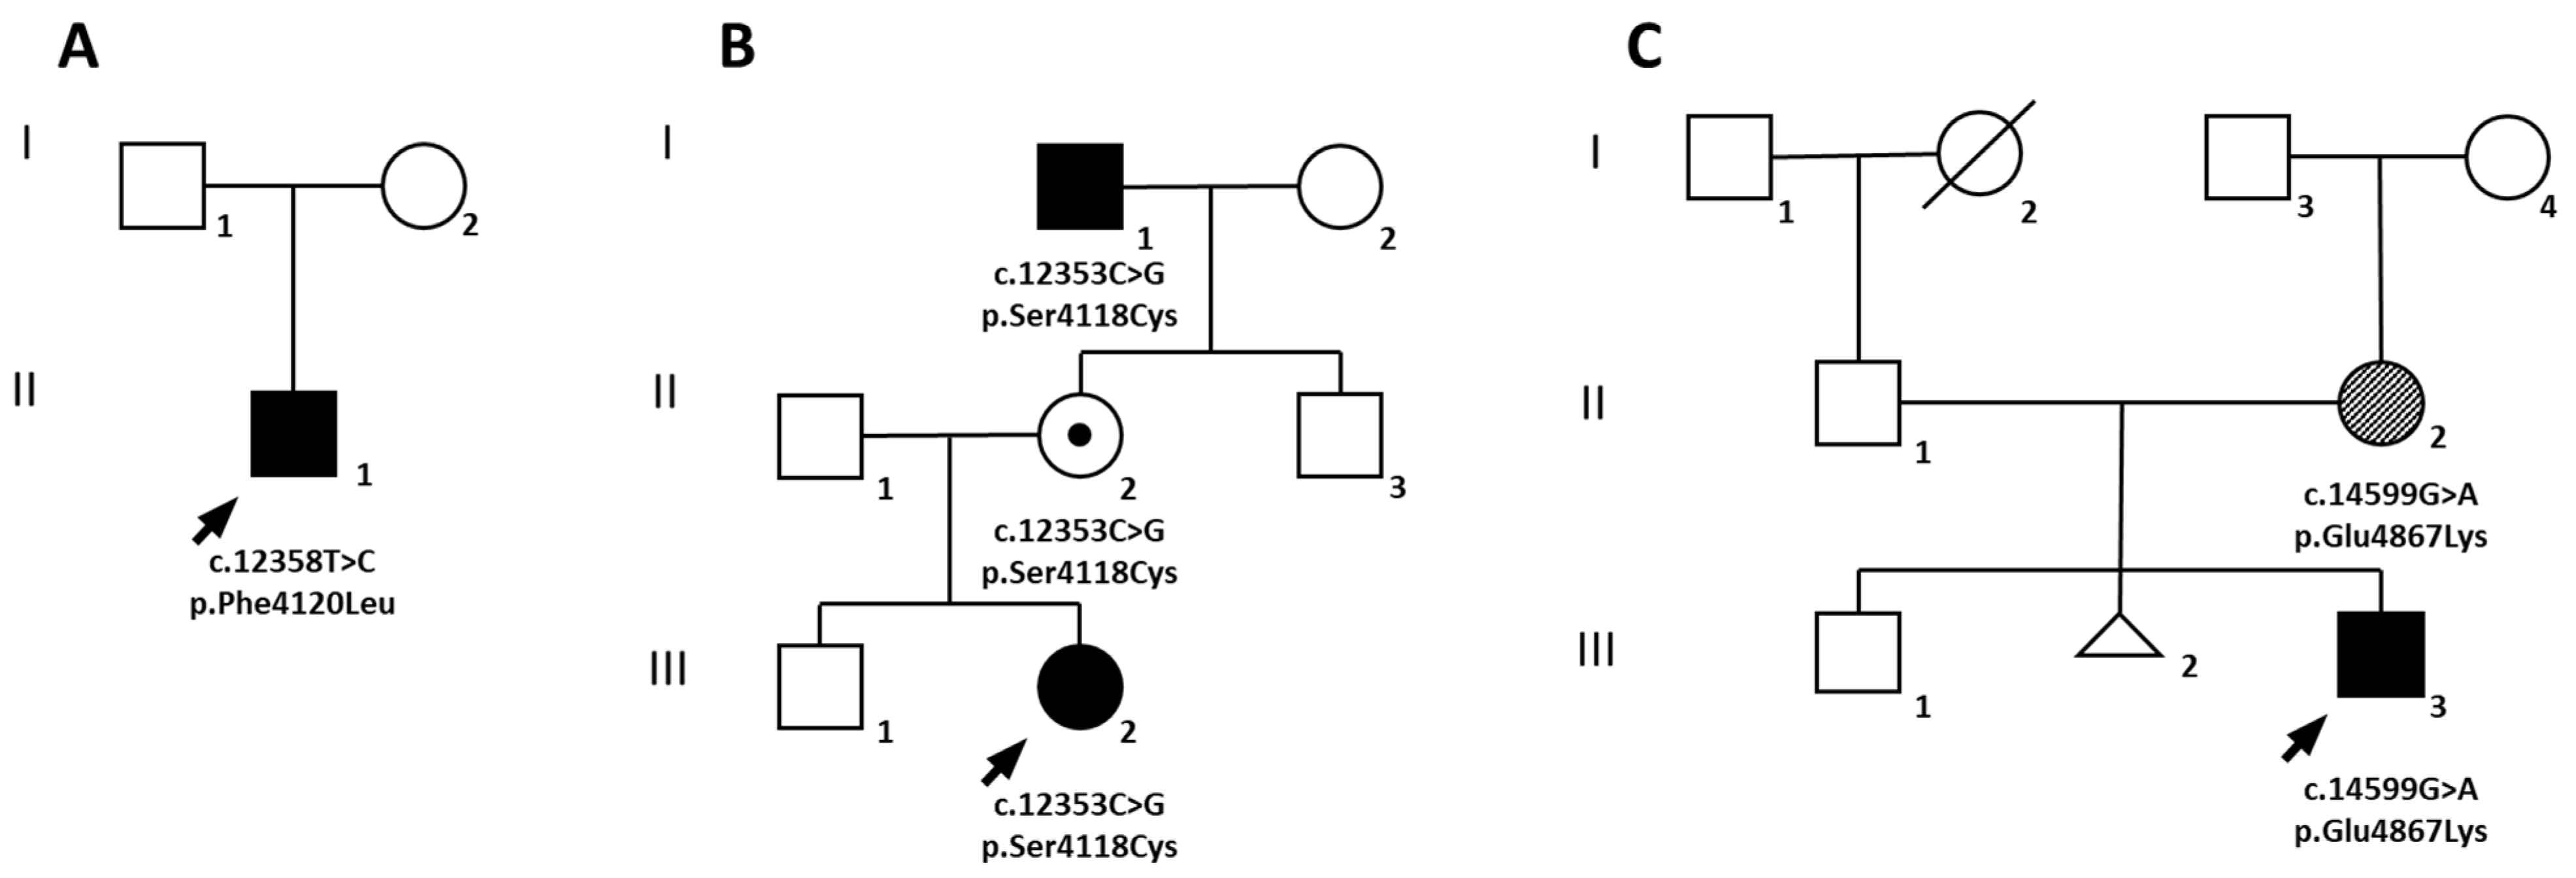

2.1. Family A

2.2. Family B

2.3. Family C

2.4. Molecular Diagnosis